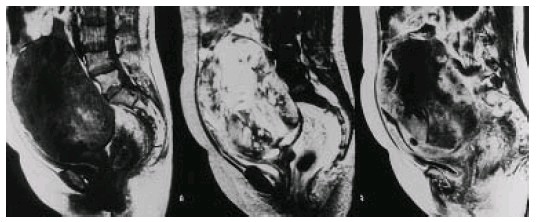

那么现在,我们是否有一个办法可以来了解子宫肌瘤是否有恶变呢?作为一个临床医生,必须要时刻关注着世界上这个领域内的研究进展,2002年,来自日本的研究者做了一项影响业界的研究,文献发表在国际妇科肿瘤杂志上。他们采用了增强延迟显像核磁共振检查的技术,结合血清乳酸脱氢酶(LDH)同工酶3的检查,发现10例子宫肉瘤的患者,在核磁共振60秒增强的图像中,10例患者都可以观察到有延迟增强的影像,而子宫肌瘤良性变性的患者,32例中仅有4例出现延迟增强的表现。10例子宫肉瘤的患者都有LDH和LDH同工酶3的升高。这个研究提示,如果联合采用增强延迟显像核磁共振检查和LDH检测,将会有助于鉴别子宫肉瘤和子宫肌瘤的良性变性。

这个研究的数量还不太大,这样的规律是否可以在更多的人群中得以重现,需要有更多的资料的验证,但是研究对于我们临床已经非常有价值,现在我已经开始采用LDH检测来筛查,必要的时候也会用增强延迟显像核磁共振检查(目前协和无此项专门检测,需要和放射科大夫进行沟通)来进行筛查。